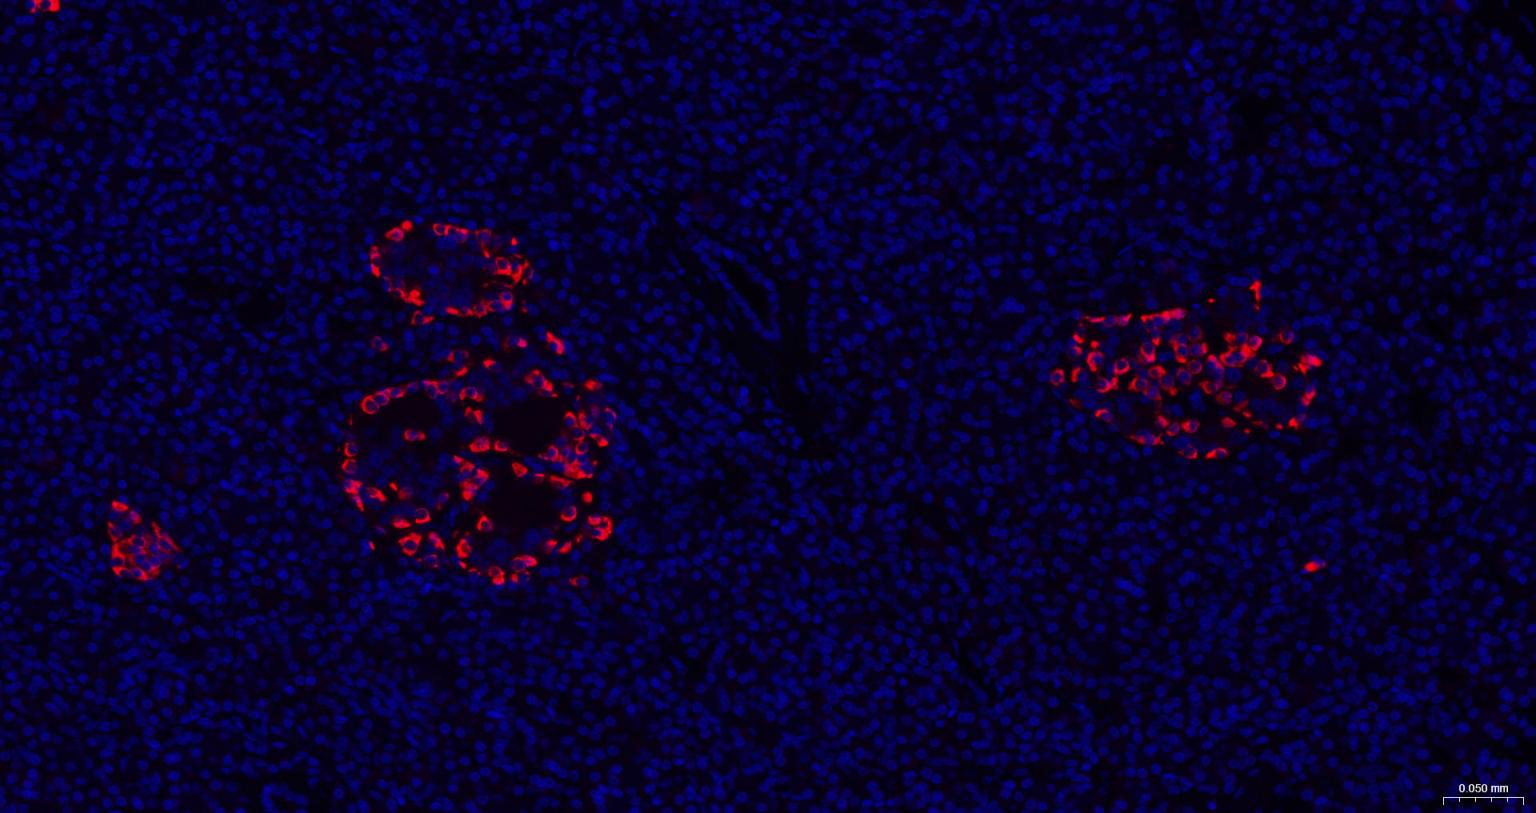

Paraformaldehyde-fixed, paraffin embedded Human Pancreas; Antigen retrieval by boiling in sodium citrate buffer (pH6.0) for 15 min; The section was incubated with Chromogranin B Polyclonal Antibody, Unconjugated (bs-0543R) at 1:200 overnight at 4°C. Followed by conjugated Goat Anti-Rabbit IgG antibody (Red, bs-0295G-BF594), DAPI (blue, C02-04002) was used to stain the cell nuclei.

Paraformaldehyde-fixed, paraffin embedded Mouse Pancreas; Antigen retrieval by boiling in sodium citrate buffer (pH6.0) for 15 min; The section was incubated with Chromogranin B Polyclonal Antibody, Unconjugated (bs-0543R) at 1:200 overnight at 4°C. Followed by conjugated Goat Anti-Rabbit IgG antibody (Red, bs-0295G-BF594), DAPI (blue, C02-04002) was used to stain the cell nuclei.